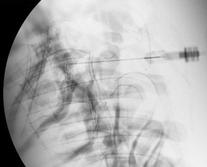

The patient lies on a special table and after appropriate intravenous sedation is administered, the skin and deeper tissues are numbed with a dentist needle and local anesthetic. A needle is then advanced under X-ray Guidance (Fluoroscopy) until reaches the epidural space in the vicinity of the nerve. Dye contrast is then injected to confirm proper placement in the exact area of the nerve inflamed and a steroid medication is injected which act as a potent anti-inflammatory medication. This will result in resolution of the inflammation and swelling of the nerve.